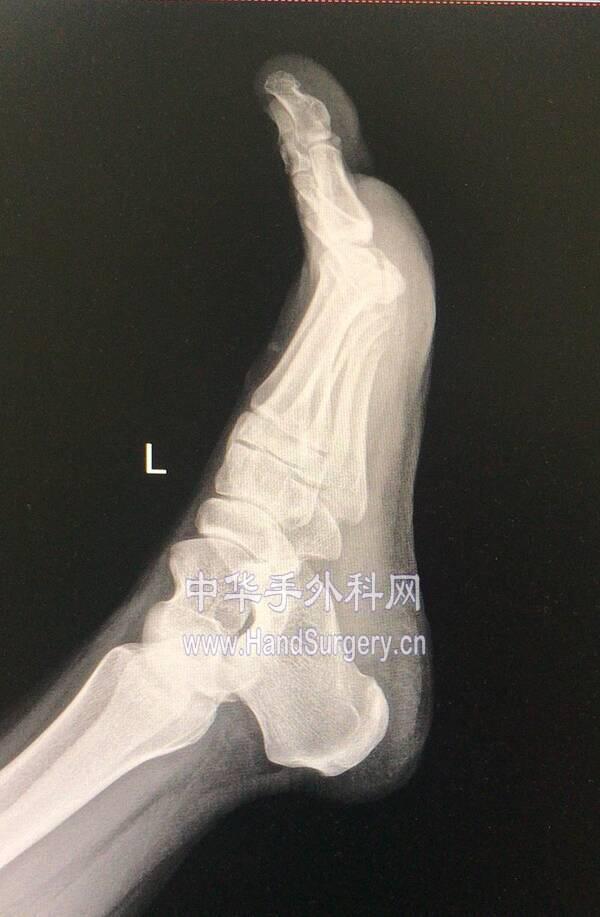

微信图片编辑_20191218175444.jpg 两侧均为中度